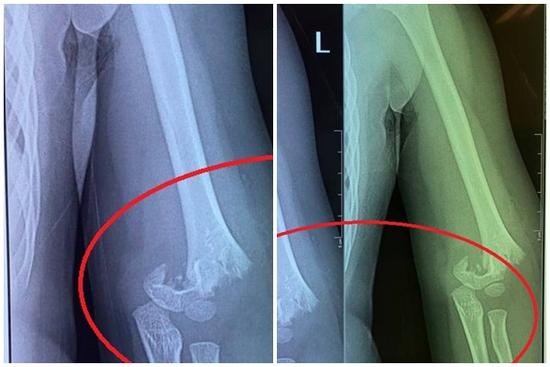

Bé gái 5 tuổi đi mẫu giáo bị bạn đẩy ngã gãy tay nhưng cô giáo không đưa đi cấp cứu ngay, người mẹ chia sẻ: Nhà trường bặt vô âm tín!

"Điều quan trọng là con bị ngã gãy tay từ sáng mà đến 12h trưa giáo viên mới cho con đi bệnh viện. Lúc con ngã, cô không đưa đi khám luôn mà lại đưa con vào lớp, để các bạn ăn uống xong xuôi rồi mới gọi một chiếc xe tư nhân đưa con đi mà không phải xe cấp cứu", chị H. bức xúc cho biết.